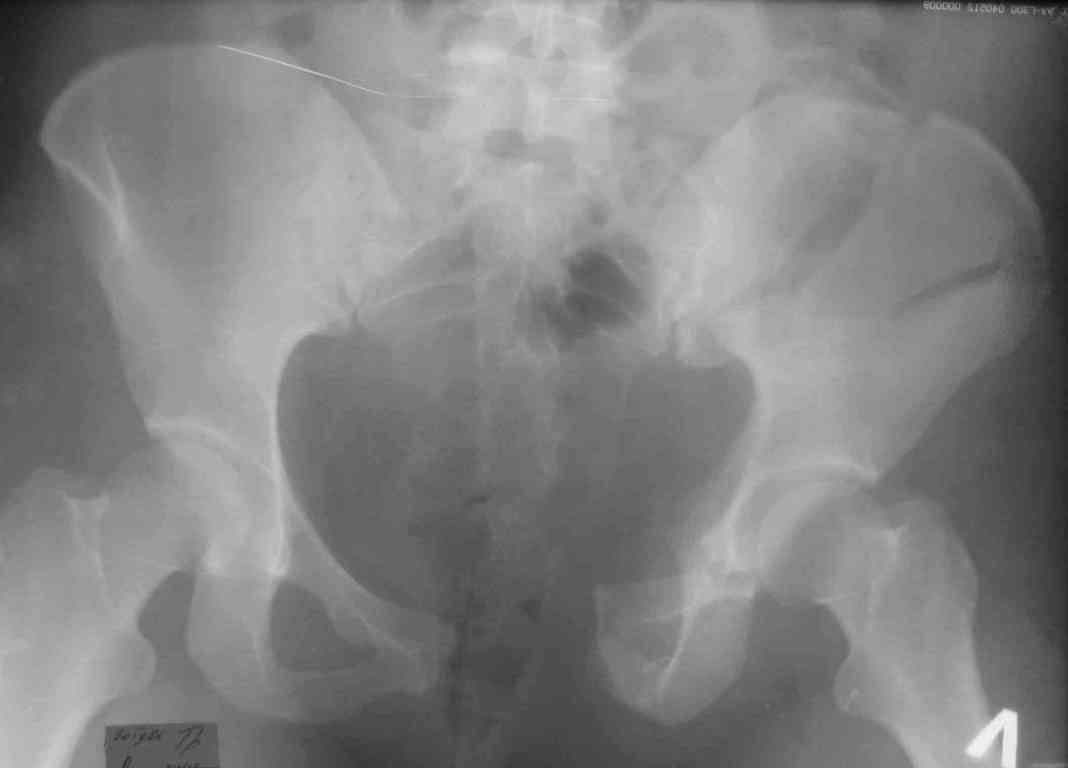

Женщина окло 30 лет, упитанная. Сочетанная травма 3 недели назад - сотрясение, ушиб груди (плюс пенвмония), мыщелок б/б (ерунда), самое тяжелое - таз.

для определения тактики лечения сделал бы КТ таза. В каком состоянии мочевыделительная система: нет ли повреждения уретры? использование АВФ мне кажется проблематичным т.к. имеется оскольчатый перелом крыла подвздошной кости слева(стержни в гребень вводить проблематично, в тело подвздошной кости- пациентка полная, имеет большой массв мягких тканей, по той же причине кольцевой аппарат будет причинять большие неудобства)предпочел бы открытую репозицию и фиксацию пластинами через подвздошный и надлобковый доступ.